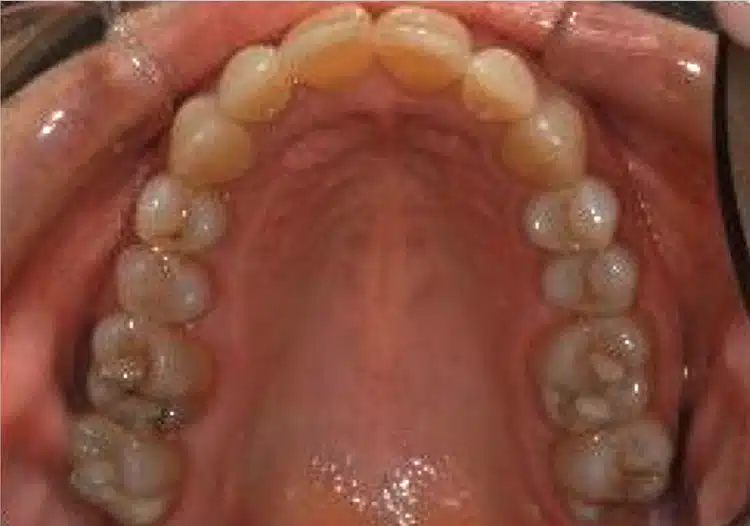

After surgically assisted osteogenic orthodontic treatment